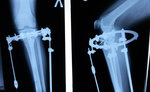

Дата операции 03.12.2015г.

Дата снятия аппаратов 09.03.2016г.

Срок лечения 95 дней.